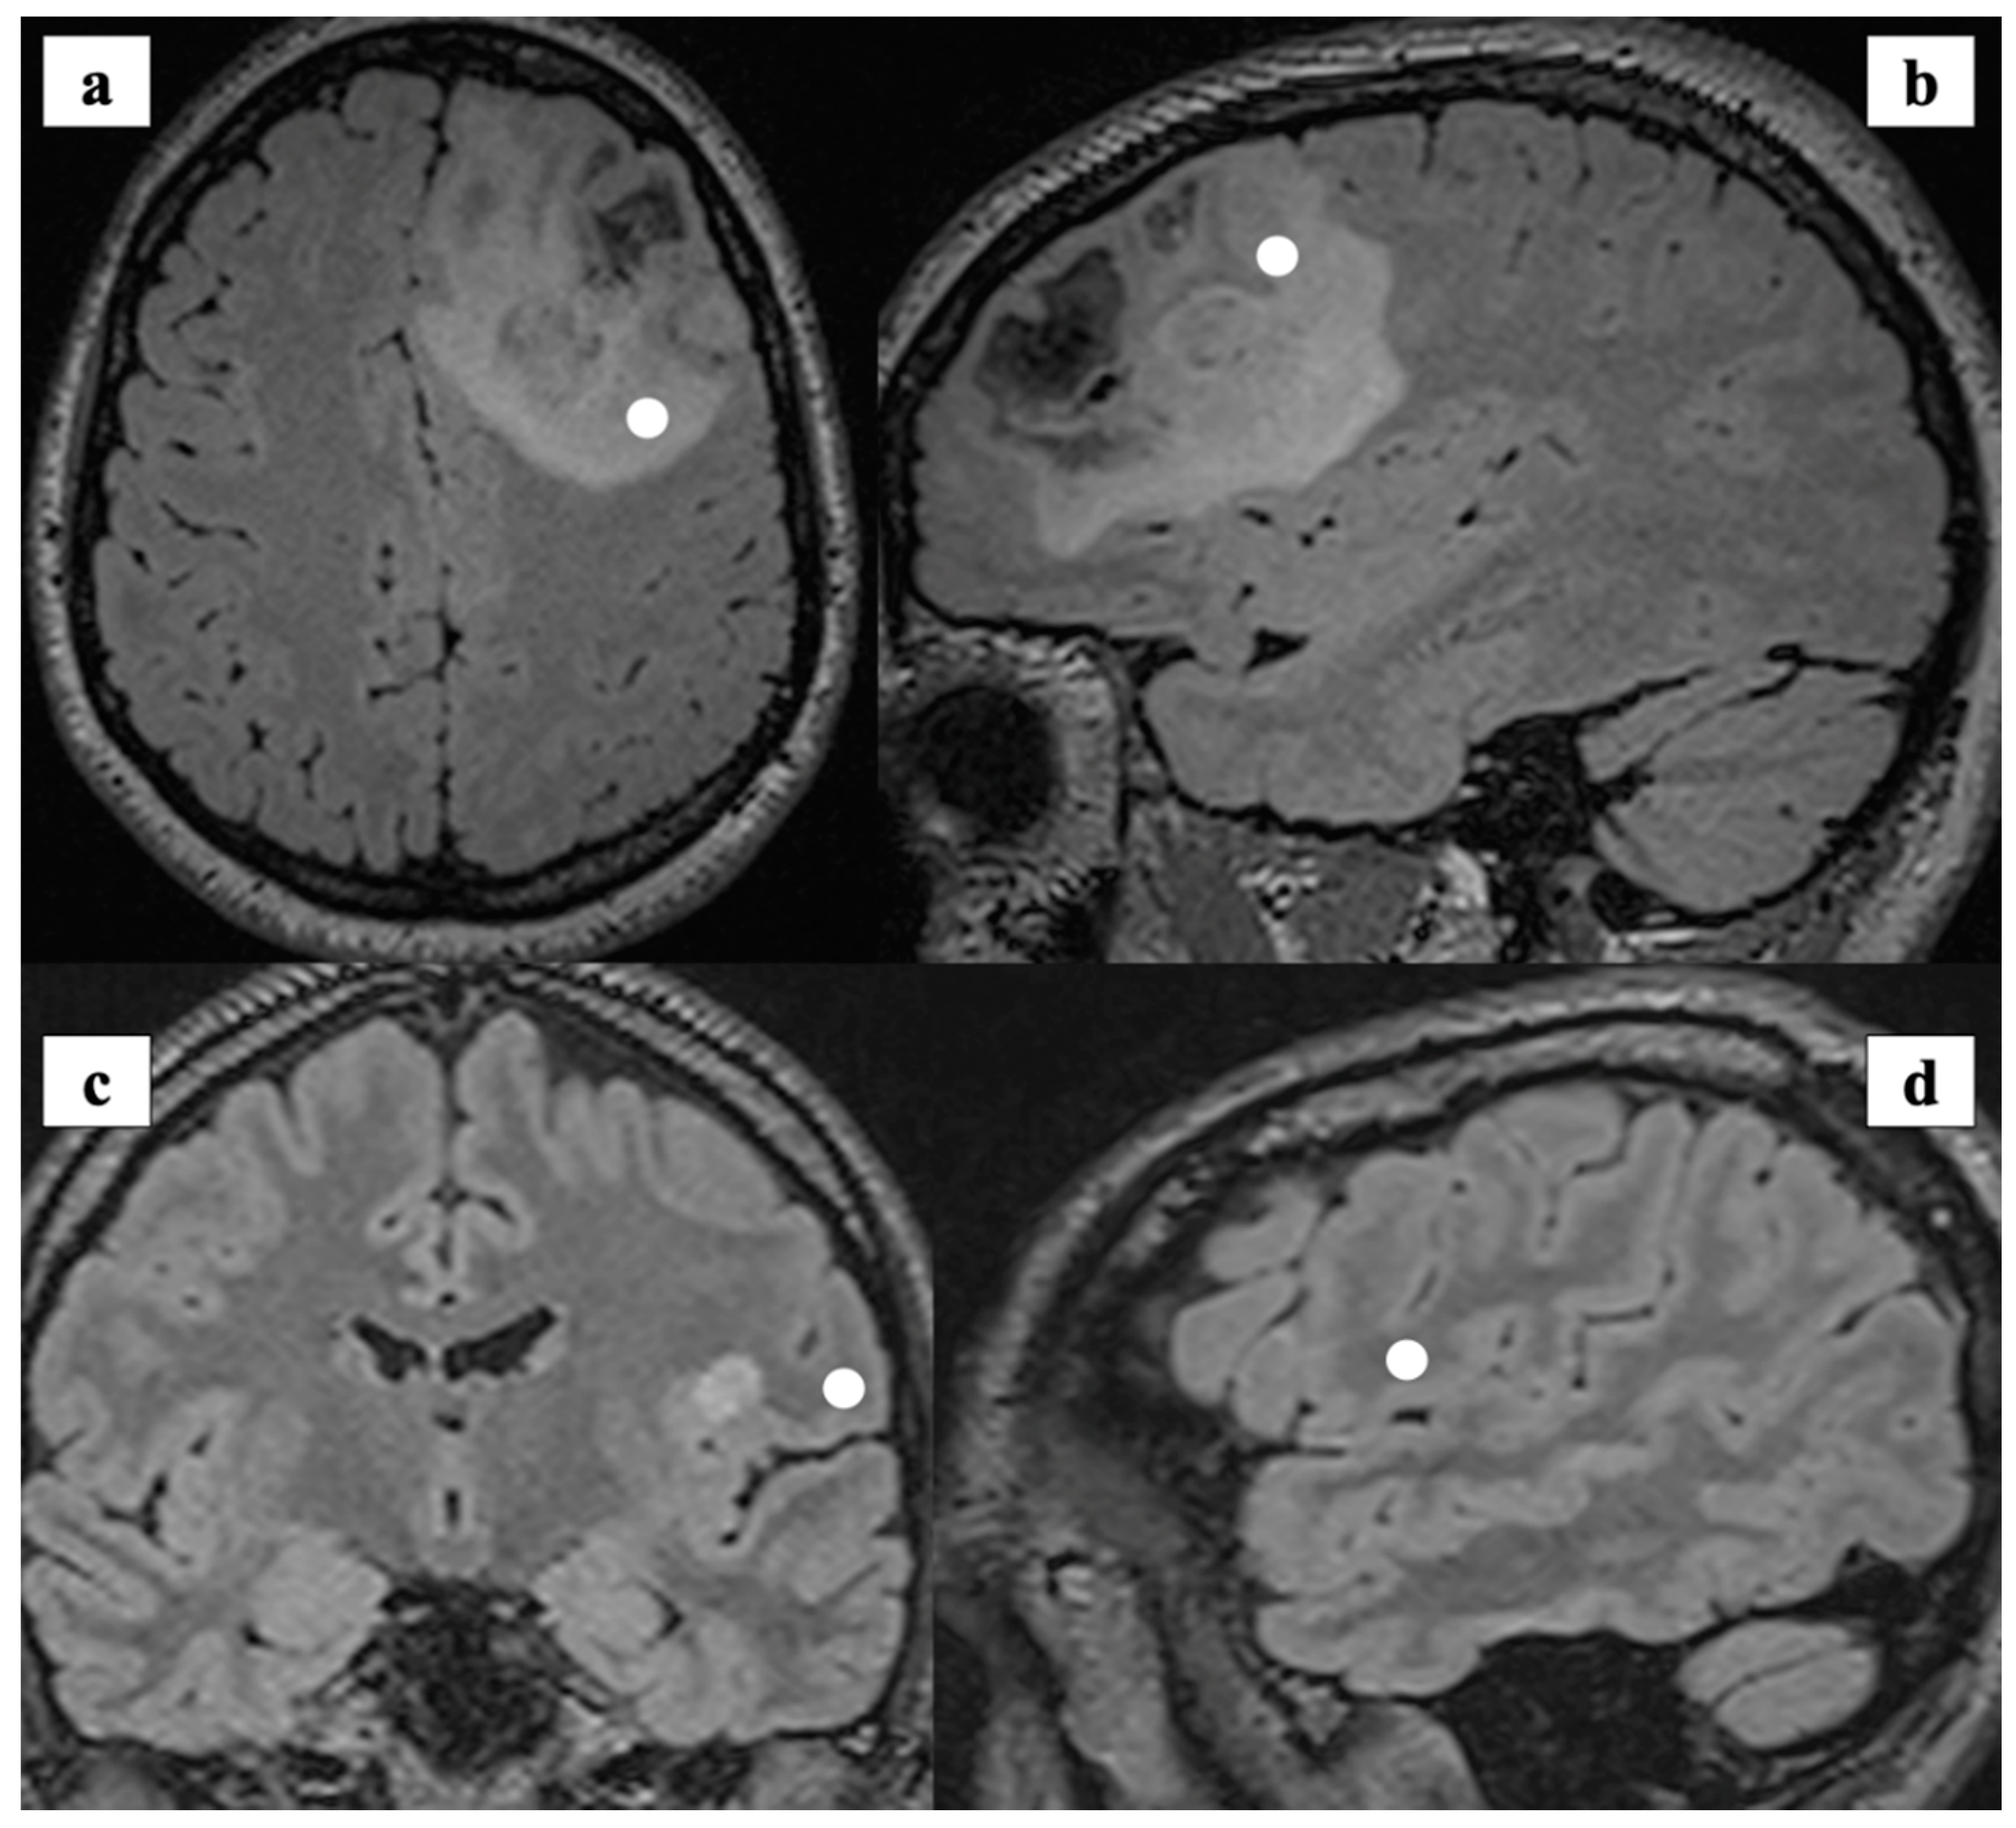

2.1. Experimental Design

2.2. Sample Preparation and Analysis